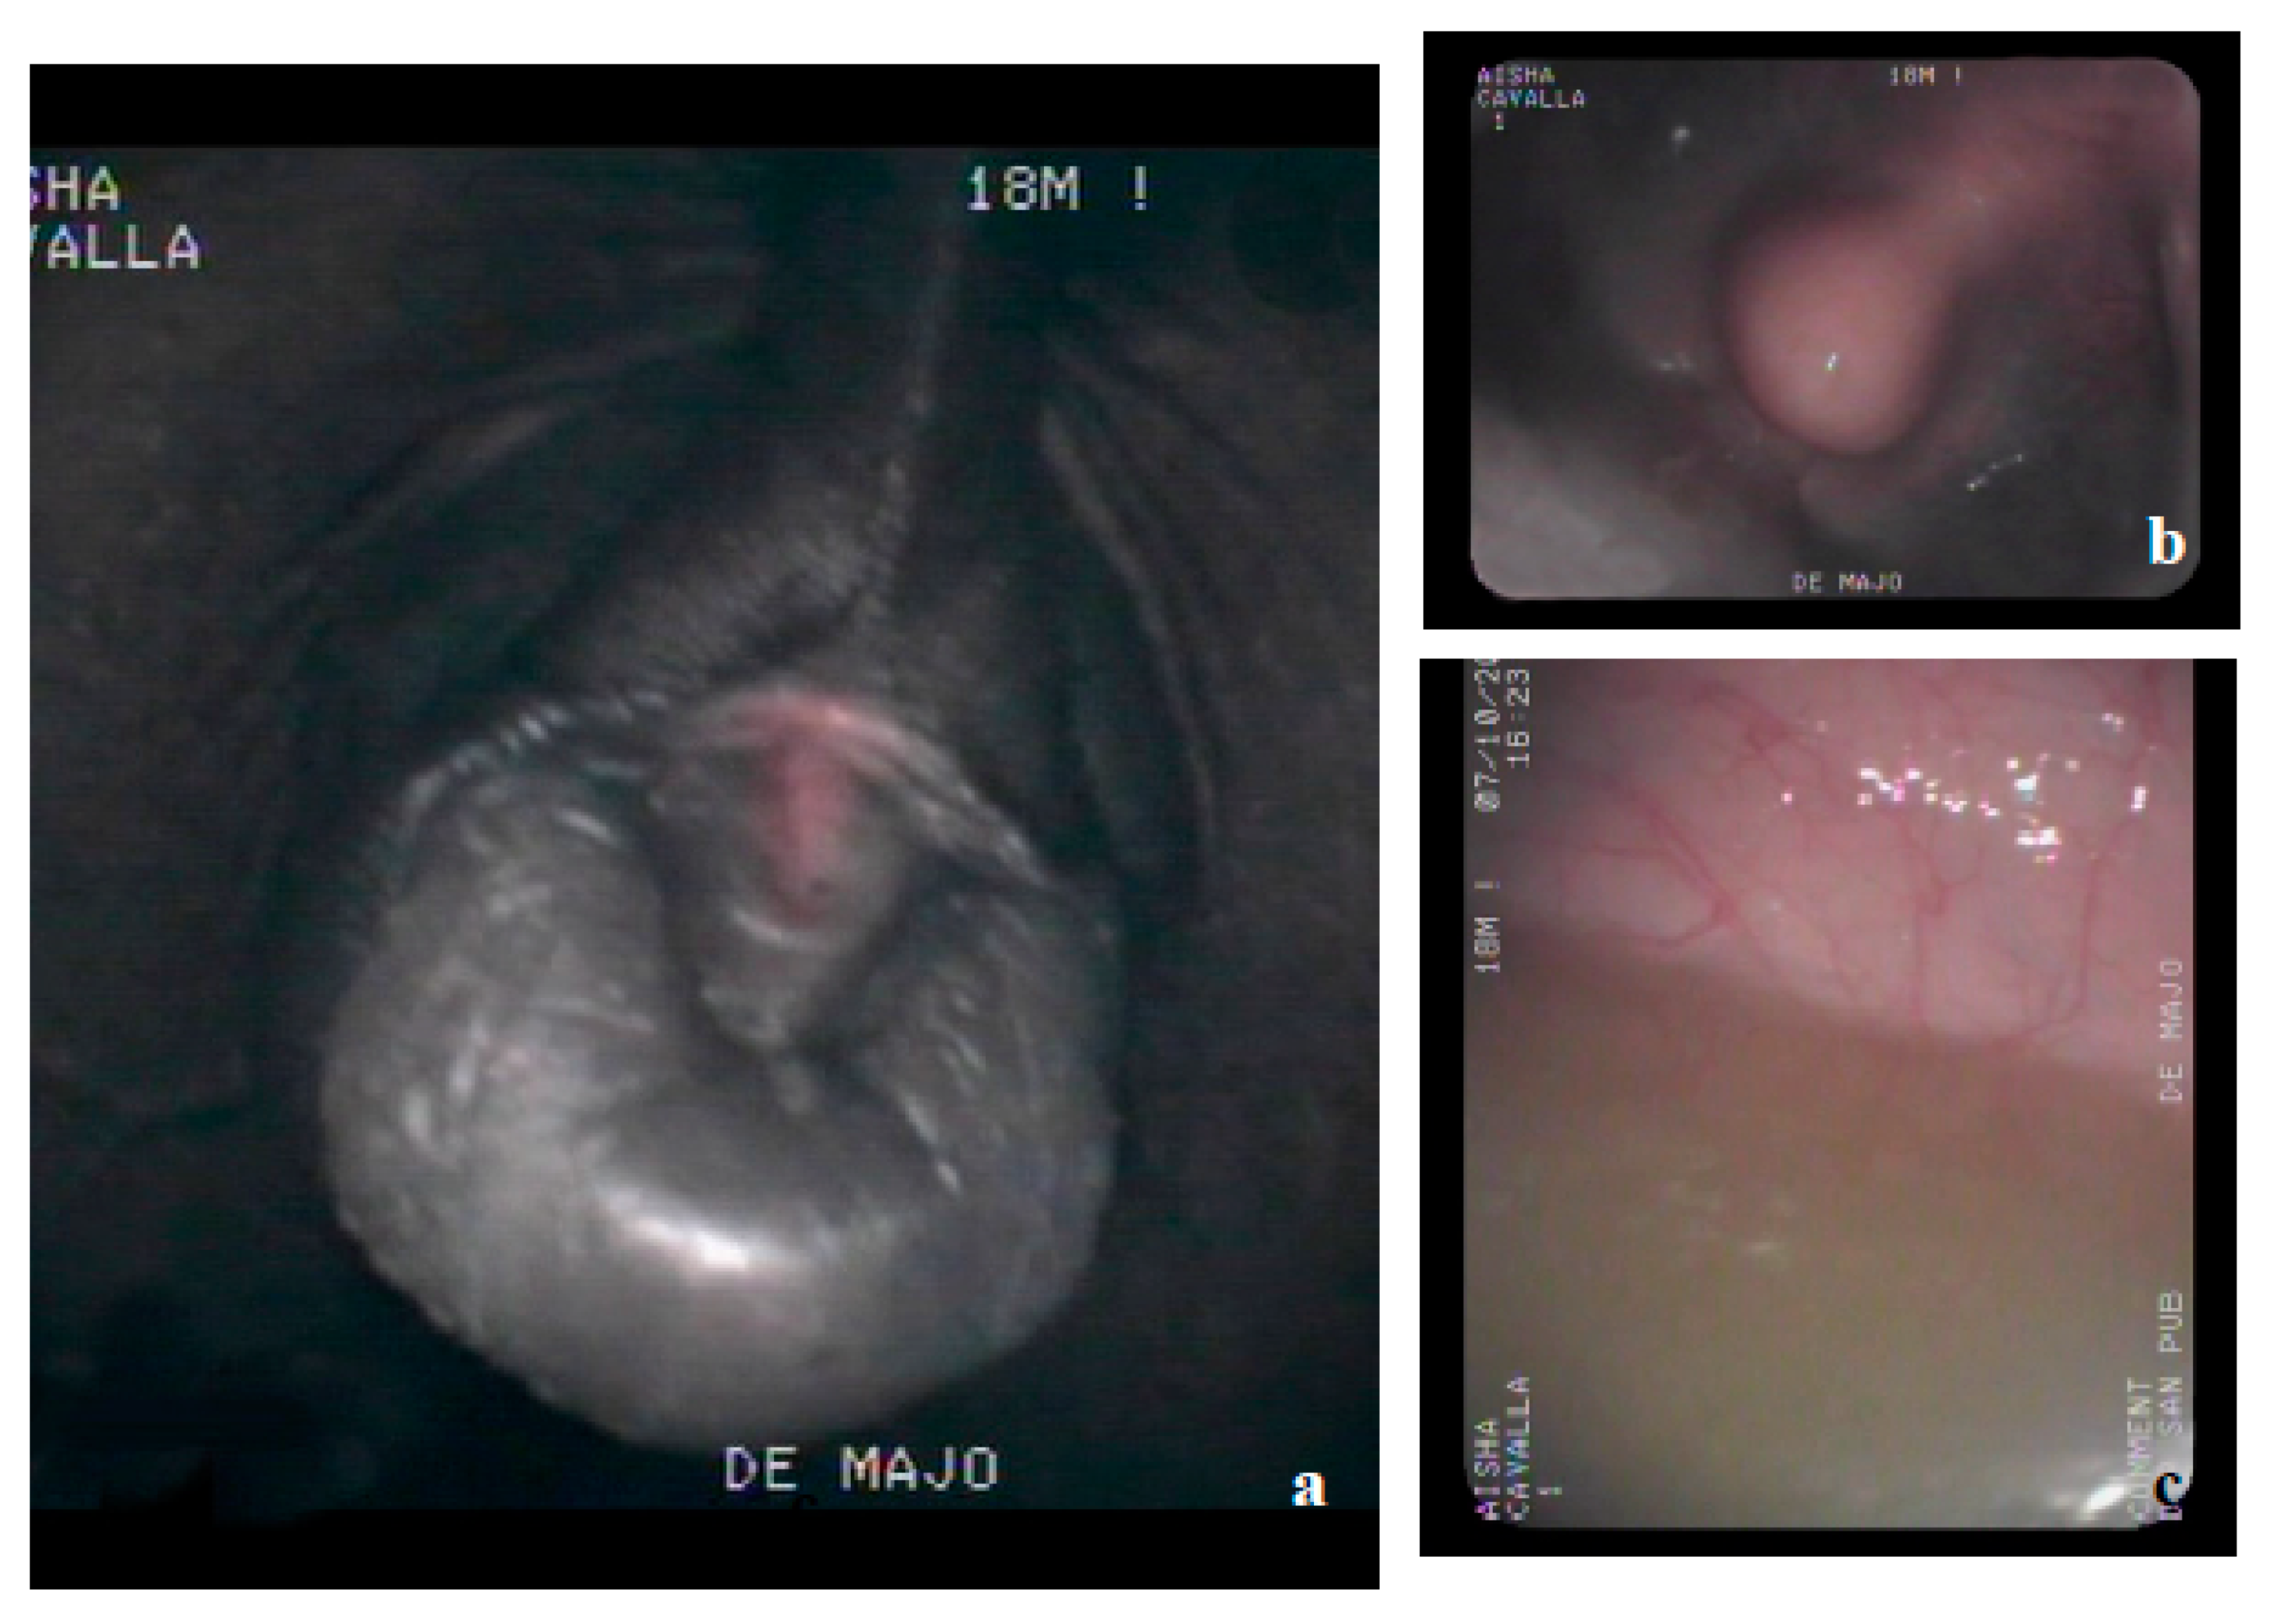

3.3. Necropsy and Anatomopathological Examination